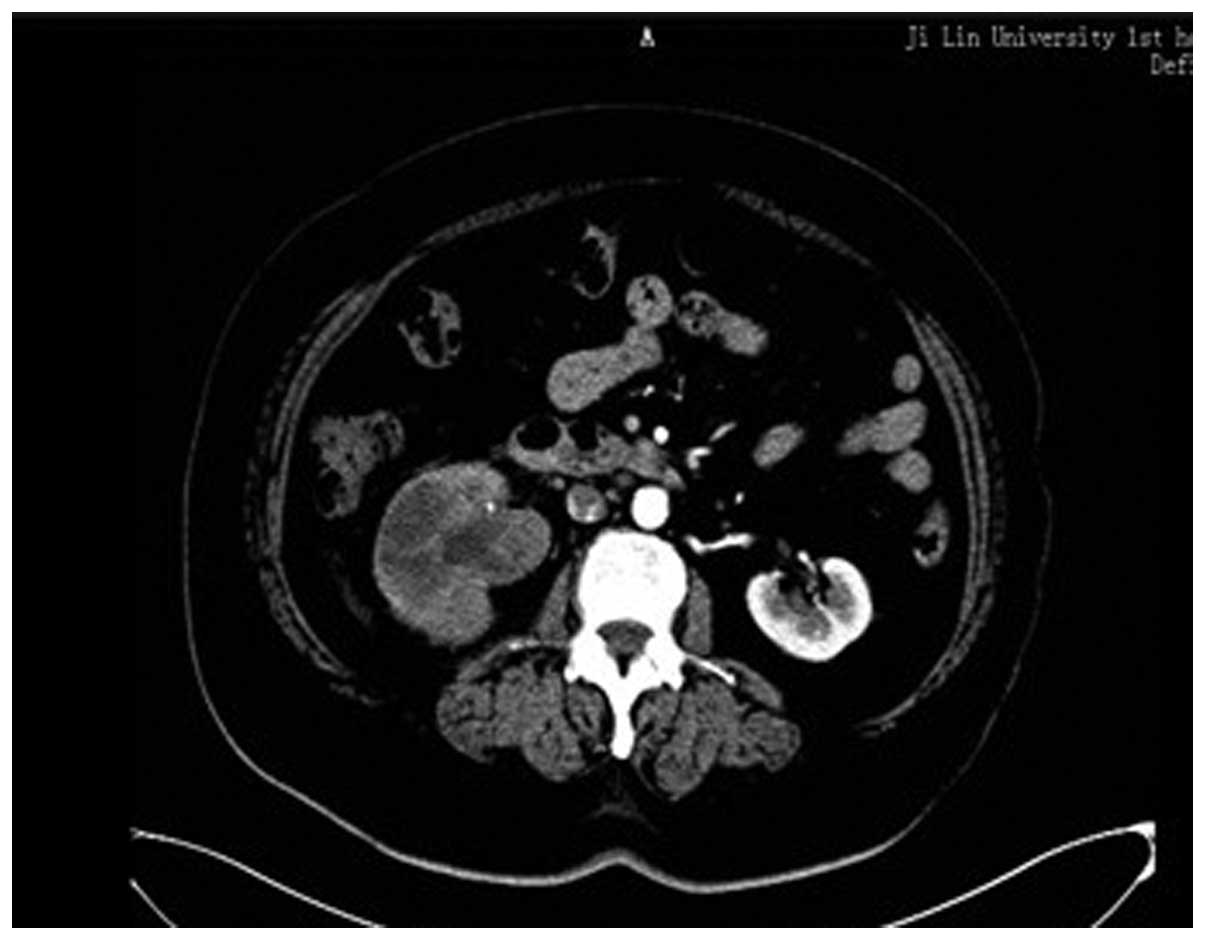

Tumor imaging and resection

Abdominal ultrasonography showed a solid, relatively well-demarcated tumor, 3.0×3.1 cm, occupying the right renal pelvis. Computed tomography (CT) showed a 2.4×2.5-cm heterogeneous and poorly-enhanced mass in the right renal pelvis (Fig. 1). The CT findings also revealed a thickened ureter wall, with irregular contrast enhancement. Cystoscopy showed no abnormalities in the urinary bladder. Retrograde pyelography could not be performed due to ureteral catheter obstruction. Further clinical analyses revealed no metastasis to other organs. Based on the clinical and radiological findings, a laparoscopic radical resection of the right kidney and an open ureterectomy were performed to remove the tumors.

Figure 1

CT scan showing a well-defined 2–3-cm mass invading the right renal pelvis. The mass shows poor contrast enhancement.